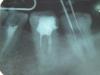

*Lena Опубликовано 4 января, 2010 Автор Поделиться Опубликовано 4 января, 2010 Уф... немного остыла, подумала и еще раз зашла сюда за советом. А можно на моем снимке показать где (в каком месте) оставлен инструмент? Есть ли перспектива у зуба "прожить" в таком состоянии? Хоть у него и нет пары вверху ? (7 и 8 удалены, 6 еле живая...) но ведь в планах протезирование, кушать то чем то нужно, хотелось бы снизу избежать проблем со съемным протезом или может быть имплантантами. (будет зависеть от финансов). И еще прикладываю "контрольный" снимок 7 месячной давности перед пломбировкой каналов, в зубе "иголочки" не этот ли инструмент там остался? И если можно, поясните полностью не грамотному человеку в стоматологии что такое медиальный канал? это справа или слева на снимке если я на него смотрю? Тут в мониторе компа? уж и не знаю как правильнее свою мысль выразить, извините за каламбур. Ссылка на комментарий

Бело4ка Опубликовано 4 января, 2010 Поделиться Опубликовано 4 января, 2010 Уф... немного остыла, подумала и еще раз зашла сюда за советом. А можно на моем снимке показать где (в каком месте) оставлен инструмент? Есть ли перспектива у зуба "прожить" в таком состоянии? Хоть у него и нет пары вверху ? (7 и 8 удалены, 6 еле живая...) но ведь в планах протезирование, кушать то чем то нужно, хотелось бы снизу избежать проблем со съемным протезом или может быть имплантантами. (будет зависеть от финансов). И еще прикладываю "контрольный" снимок 7 месячной давности перед пломбировкой каналов, в зубе "иголочки" не этот ли инструмент там остался? И если можно, поясните полностью не грамотному человеку в стоматологии что такое медиальный канал? это справа или слева на снимке если я на него смотрю? Тут в мониторе компа? уж и не знаю как правильнее свою мысль выразить, извините за каламбур. Медиальный корень - это тот, который ближе к 5. В нём 2 канала. В одном из них вероятно есть отломок инструмента. На снимке с иглами его или ещё нет, или игла прям до него доходит, но 100% утверждать не берусь. А вот на снимке, где иголок нет, очень похоже. Эндодонтические инструменты ломаются в процессе работы и у опытных врачей. За это доктору голову рубить не стоит. Просто теперь нужно искать другой путь выхода из сложившейся ситуации. Каждый доктор выберет свой в соответствии со своими знаниями и умениями. Медиальный корень - это тот, который ближе к 5. Ну или к 7. А на мониторе - левый. Ссылка на комментарий

zybnaya feya Опубликовано 4 января, 2010 Поделиться Опубликовано 4 января, 2010 (изменено) Уф... немного остыла, подумала и еще раз зашла сюда за советом. А можно на моем снимке показать где (в каком месте) оставлен инструмент? Есть ли перспектива у зуба "прожить" в таком состоянии? Хоть у него и нет пары вверху ? (7 и 8 удалены, 6 еле живая...) но ведь в планах протезирование, кушать то чем то нужно, хотелось бы снизу избежать проблем со съемным протезом или может быть имплантантами. (будет зависеть от финансов). И еще прикладываю "контрольный" снимок 7 месячной давности перед пломбировкой каналов, в зубе "иголочки" не этот ли инструмент там остался? И если можно, поясните полностью не грамотному человеку в стоматологии что такое медиальный канал? это справа или слева на снимке если я на него смотрю? Тут в мониторе компа? уж и не знаю как правильнее свою мысль выразить, извините за каламбур. *Lena' ,простите за прямоту,но скажу. Доктор который измеряет длину иглами Миллера(это ТАКОЙ совок) не пользуясь апекслокатором и коффердамом,я про мед обработку уже могу докадываться-добра вашим зубам не сделает и тем более не исправит данную ситуацию. У нее просто нет на это подходящего оборудования. Обломанный инструмент не приговор. Сложно его конечно вытащить или в лучшем случае обойти,но можно. НО! Для этого нужен ультразвуковой наконечник с специальными насадками и машинная эндодонтия. Повторюсь-ищите доктора с нормальным оснащением и знаниями. Изменено 4 января, 2010 пользователем zybnaya feya Ссылка на комментарий